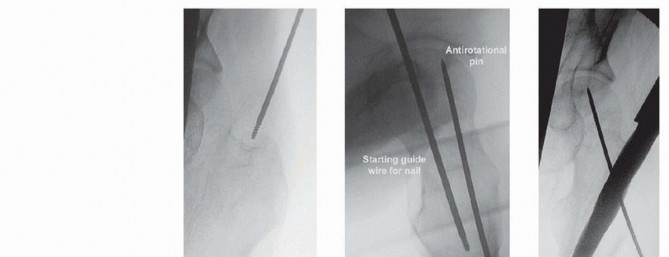

TECH FIG 4 • Landmarks for cephalomedullary nail placement. The iliac crest is marked and the trochanter is outlined. The incision is in line with the femoral shaft and several centimeters proximal to the tip of the trochanter. This can be done by a Smith-Petersen or Watson-Jones approach, as described earlier. An antirotational pin may be used to maintain reduction ( TECH FIG 5B,C). Once reduction has been obtained, the entry reamer is introduced ( TECH FIG 5D). For a short cephalomedullary nail, the entry reamer is all that is needed before nail passage. If a long cephalomedullary nail is being placed, serial reaming can be performed to 1 to 1.5 cm over the desired nail diameter. ### Proximal and Distal Interlocking After the nail is positioned at the correct depth, the guidewire into the femoral head is placed. Multiple fluoroscopic images are needed to make sure the tip of the guidewire is placed within the center of the femoral head for nails with a single screw going into the head. Newer nails with more than one screw going into the head may necessitate adjustments to this technique to allow passage of both screws (such as placing the first lag screw slightly superior to center to allow passage of the second screw inferior to center). A depth gauge is used to check the length of the guidewire. For rotationally unstable femoral neck fractures, an antirotational guidewire or screw can be placed to prevent rotation of the fracture with tapping ( TECH FIG 6A). Many nail systems allow a pin to be placed through a sheath attached to the jig or have an antirotational bar. A reamer is then used to open the outer cortex of the femur and is continued into the head under fluoroscopic guidance. The reamer should be checked during passage to ensure the guidewire is not being driven into the pelvis and the reduction is not lost during reaming. The lag screw is then tapped, and fluoroscopy is again used to ensure the reduction is not lost. The lag screw is placed and fluoroscopy undertaken in multiple views to rule out penetration of the subchondral surface. If a distal interlock is desired, it is then placed. Most nail systems have a set screw that needs to be advanced to give rotational control to the lag screw. If compression is desired, the set screw then needs to be loosened, usually a quarter-turn of the screwdriver, according to the recommendations of the individual nail system being used. As mentioned earlier, appropriate films should be taken with the patient aslee This may include plain films if fluoroscopy is not adequate ( TECH FIG 6B,C). 383

### TECH FIG 5 • A. Intraoperative AP fluoroscopic view showing starting point at medial edge of greater trochanter, in line with the mid-axis of the intramedullary canal. B. Intraoperative photograph showing longer incision distally used to obtain anatomic reduction with temporary stabilization pin placed to maintain reduction. C. Intraoperative lateral fluoroscopic view showing position of the temporary stabilization pin and the guidewire. D. Intraoperative AP fluoroscopic view showing the entry reamer with antirotational pin maintaining reduction of fracture.

### TECH FIG 6 • A. Antirotational screw is placed in addition to guidewire before tapping when using a sliding hip screw or cephalomedullary nail. B. Preoperative radiograph showing a displaced femoral neck fracture. C. Final intraoperative AP fluoroscopic view showing anatomic reduction with antirotational screw with cephalomedullary nail.